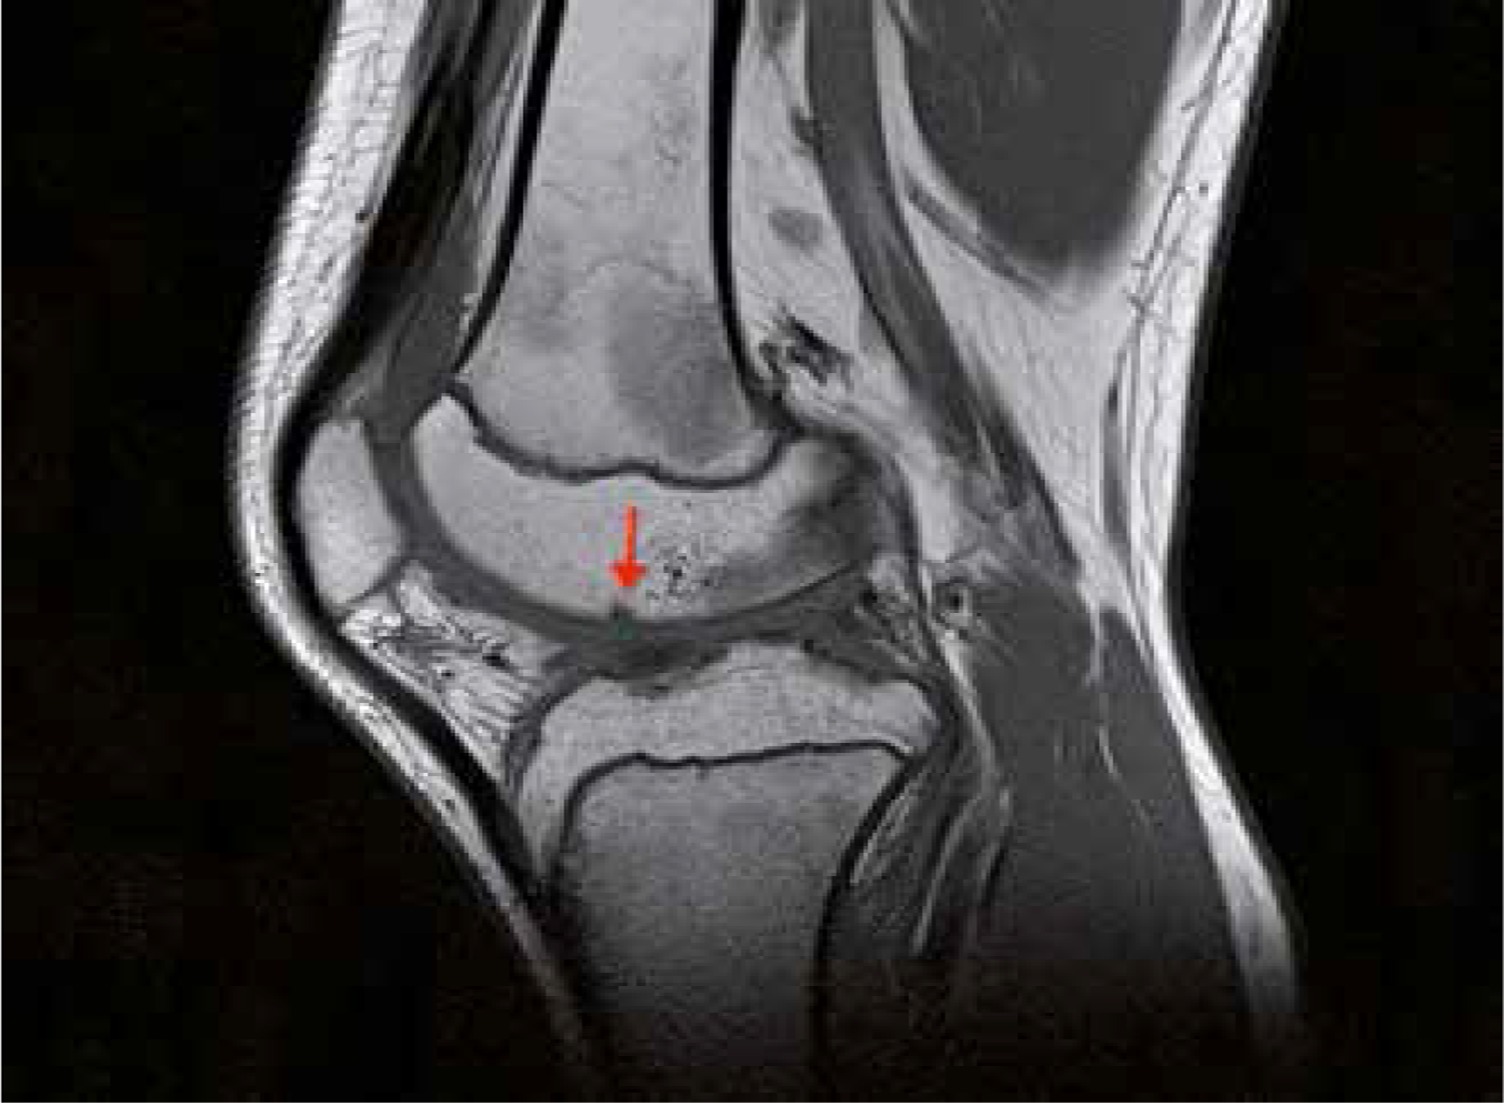

From www.oarsijournal.com

Associations between MRIdefined structural pathology and generalized Arthritis Under Knee Knee arthritis occurs when the cushioning cartilage in the joint wears down, making the knee stiff and painful with certain movements. There are three types of knee arthritis: There are many types of treatments, ranging from heat or cold therapy,. Osteoarthritis causes the cartilage in your knee joint to thin and the surfaces of the joint to become rougher, which. Arthritis Under Knee.

From www.termedia.pl

resonance imaging of the knee joint in juvenile idiopathic Arthritis Under Knee There are many types of treatments, ranging from heat or cold therapy,. Osteoarthritis (oa) of the knee is a common condition that causes pain, inflammation, and stiffness in the knee joint. Treatment typically involves physical therapy and other. There are three types of knee arthritis: Who gets osteoarthritis of the knee? Knee arthritis occurs when the cushioning cartilage in the. Arthritis Under Knee.